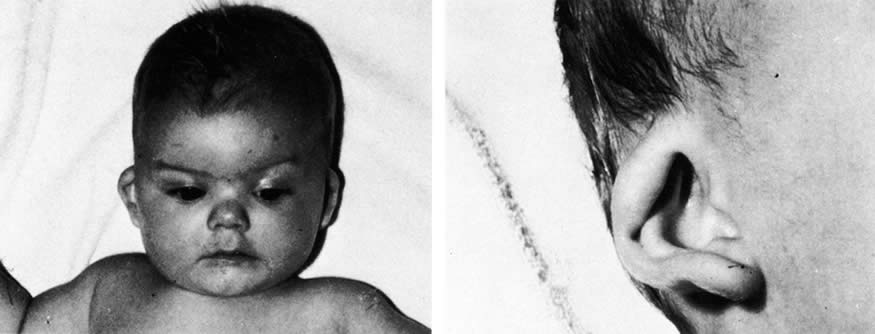

acid. N Engl J Med 300:329, 1979 116. Lammer EJ, Chen DT, Hoar RM, et al: Retinoic acid embryopathy. N Engl J Med 313:837, 1985 117. Fernhoff PM, Lammer EJ: Craniofacial features of isotretinoin embryopathy. J Pediatr 105:595, 1984 118. Lott IT, Bocian M, Pribram HW, et al: Fetal hydrocephalus and ear anomalies associated with maternal use of isotretinoin. J Pediatr 105:597, 1984 119. Hall JG: Vitamin A: A newly recognized human teratogen. Harbinger of things to come. J Pediatr 105:583, 1984 120. De La Cruz E, Sun S, Vangvanichyakorn K, et al: Multiple congenital anomalies associated with maternal isotretinoin therapy. Pediatrics 74:428, 1984 121. Lammer EJ: Embryopathy in infant conceived one year after termination of maternal

etretinate. Lancet 2:1080, 1988 122. Lenz W: Thalidomide and congenital abnormalities. Lancet 1:45, 1962 123. McBride WG: Thalidomide and congenital abnormalities. Lancet 2:1358, 1961 124. Miller MT, Stromland K: Teratogen update: thalidomide: A review, with a focus on ocular findings

and new potential uses. Teratology 60:306, 1999 125. Thiersch JB, Phillips FS: Effect of 4-amino-pteroylglutamic acid (aminopterin) on